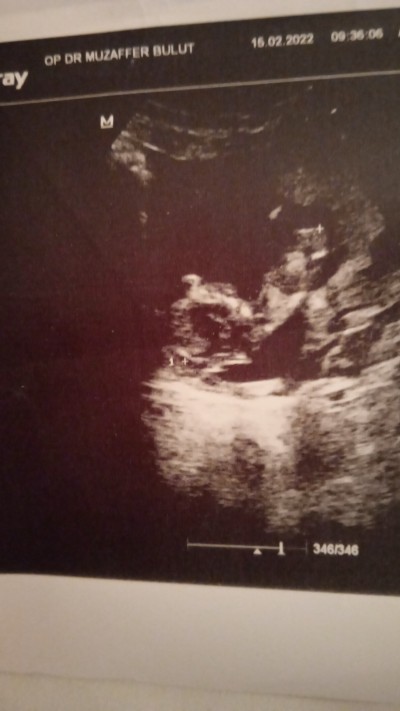

13 +2 haftalık hamileyim bebeğimi çok merak ediyorum ilk hamileligim ultrason resmi var cinsiyetini anlayan varmi

Gebelik haftası 13+2